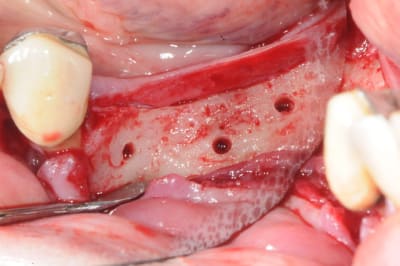

pxav écrivait:

--------------

> ou bien une comme ça:

>

> --

ou comme ça encore...

( agénésie de 12 - expansion osseuse sur une crête fine ) agénésie...

la suite à Sallanches les 2 et 3 Février pour ceux qui veulent encore s’inscrire)

11/12/2011 à 13h50

très beau!

joli bombé vestibulaire, il va falloir que je fasse fort pour rester devant!

:-))

--

xbk

"Si tous ceux qui croient avoir raison n'avaient pas tort, la vérité ne serait pas loin" Dac Pierre

voici peut être une autre solution qui te satisfera d'avantage car beaucoup plus simple à mettre en œuvre.

c'est une simple ROG avec des vis pour maintenir l'espace sous la membrane.

13/12/2011 à 05h00

tu as utilisé le ballonnet pour obtenir la laxité de la muqueuse ?

13/12/2011 à 05h02

oups ! j'avais oublié les opt

merci à ceux qui ont déja pratiqué cette technique de me dire quel est leur mode opératoire. les résultats, les p'tits trucs pour faire avancer la science quoi ...